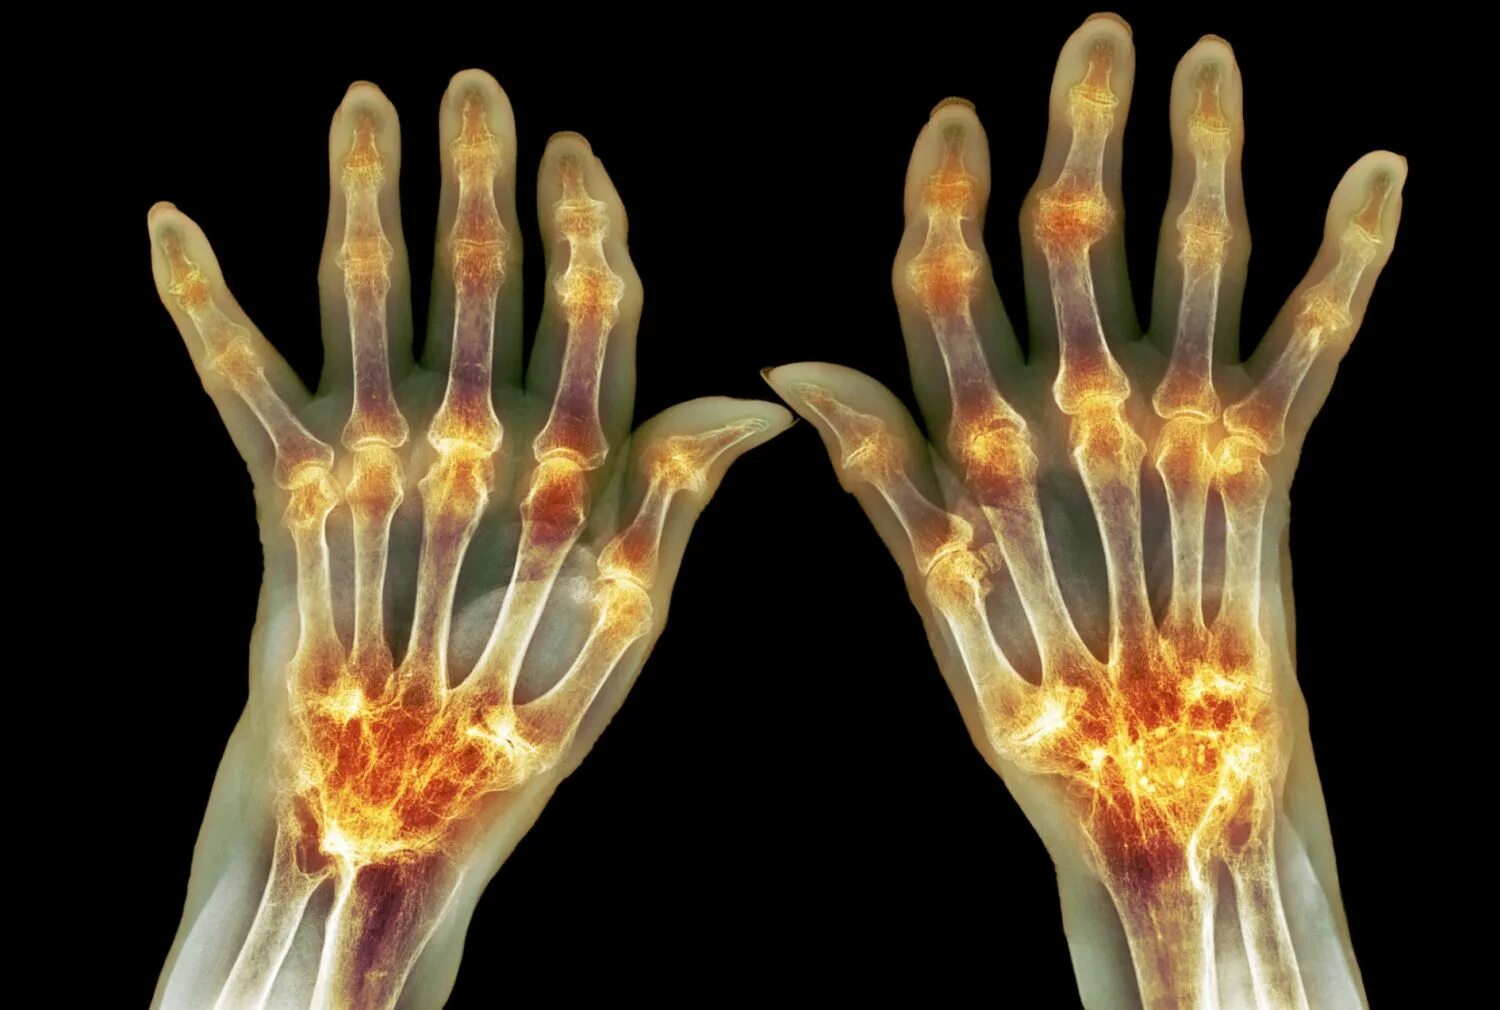

Ревматизм ног